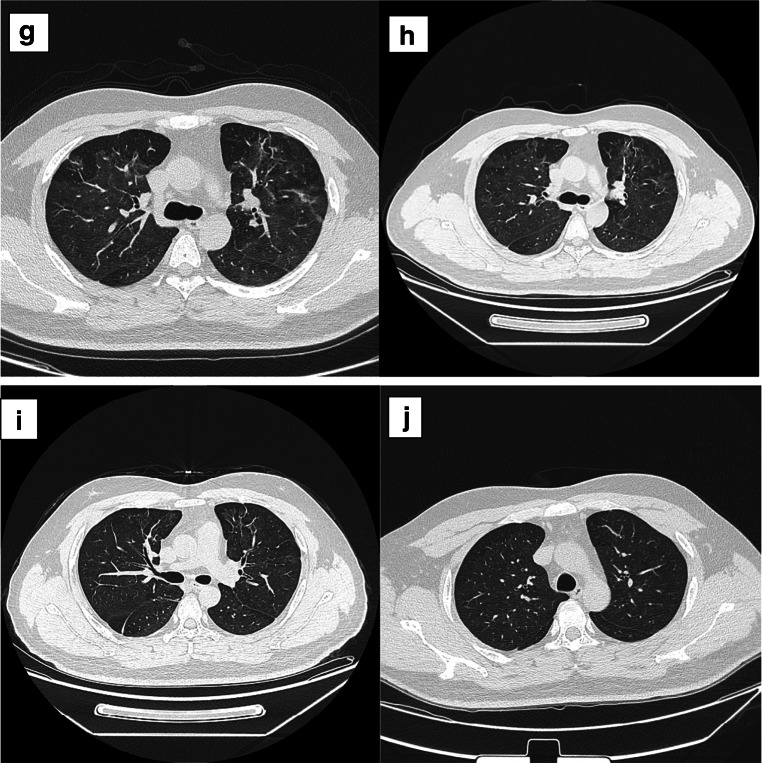

Fig. 1.

Chest CT of the patient. a Chest CT on January 19. b Chest CT on January 23. c Chest CT on January 25. d Chest CT on January 27. e Chest CT on February 22. f Chest CT on March 1. g Chest CT on March 9. h Chest CT on March 1. i Chest CT on April 17. j Chest CT on May 25

In the local hospital, chest CT showed that there were infectious lesions in both lungs on February 22th, and the lesions were partially fibrotic (Fig. 1e). Continue to give anti-virus, anti-infection and supportive treatment (the treatment scheme is the same as above), and the patient’s physical state and mental state gradually return to normal. Chest CT showed infectious lesions in both lungs. On March 1th, the lesion area was small and some lesions were fibrous (Fig. 1f). He got better and was discharged from hospital without coughing or vomiting. The patient was closely monitored at home and did not receive special treatment for 14 days. After mild exercise in isolation period, symptoms such as dizziness, chest tightness, dry cough, and shortness of breath appeared. The patient was hospitalized again on March 9th. Chest CT showed that both lungs had infectious lesions, which were smaller than the previous tests (Fig. 1g). The expert consultation of Shanxi Medical Team gave the patients TCM treatment, but the specific plan was not clear. As the above symptoms were obviously relieved, SARS-CoV-2 nucleic acid test was negative on March 9th and 11th, and he was discharged from hospital. In the next few days, he was left at home for observation and isolation. During the follow-up, he experienced chest discomfort after activities. One week later (March 20th), the patient received chest CT examination again (Fig. 1h); the results showed that the lesions were less than before. Serological tests showed that both antiviral antibodies and antiviral antibodies were positive (Table 2).

Four weeks later (April 17th), the patient’s virus-specific IgM became negative, but IgG was still positive (Table 2). On April 17th, chest CT was reexamined, showing that the area of lung lesions decreased and the density increased compared with before (Fig. 1i). The serological test results of IgG and IgM in patients on May 8 and May 25 were the same as last time (Table 2). On May 25th, chest CT examination showed that there were many strip-shaped and sheet-shaped high-density lesions in both lungs, accompanied by pleural adhesion; the lesion scope was smaller than before, and the partial density decreased (Fig. 1j). On July 20th, patients’ IgG was still positive (Table 2), and the cut-off index (COI) value of IgG detected by chemiluminescence immunoassay (CLIA) was 8.17 (reference range < 1.0 COI). During the follow-up, the antibody was continuously positive (Table 2).